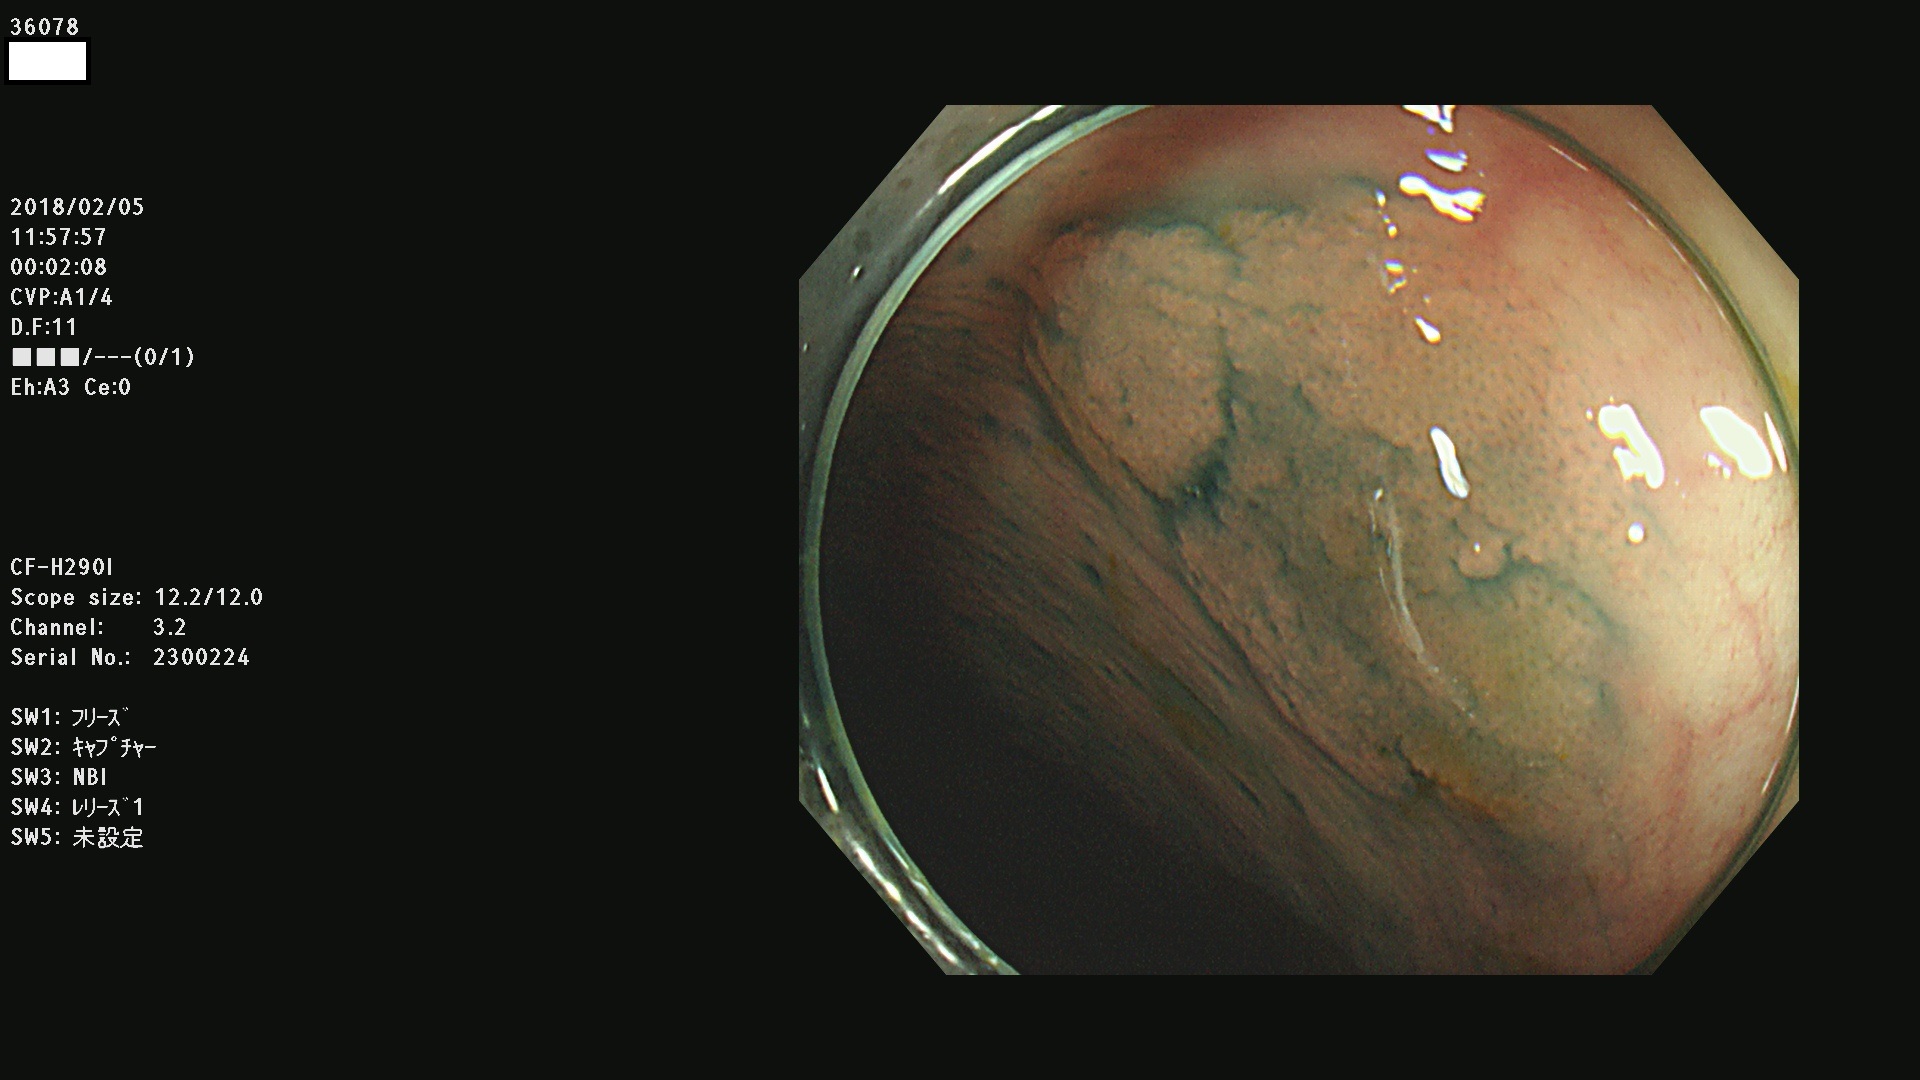

36000 36001 36003 36004 36008 36009 36012 36013(SSA/Pのみ) 36015 36016 36017 36021 36022 36023 36027 36030 36033(SSA/Pのみ) 36036 36037 36042 36044 36045 36046 36047 36051 36053 36054 36055 36056 36057 36058 36059 36060 36061 36062 36073(SSA/Pのみ) 36074 36075 36076 36078 36081 36082 36083 36089 36090(SSA/Pのみ) 36094 36096

発見困難で危険性の高い平坦型病変(上記100名より抽出)